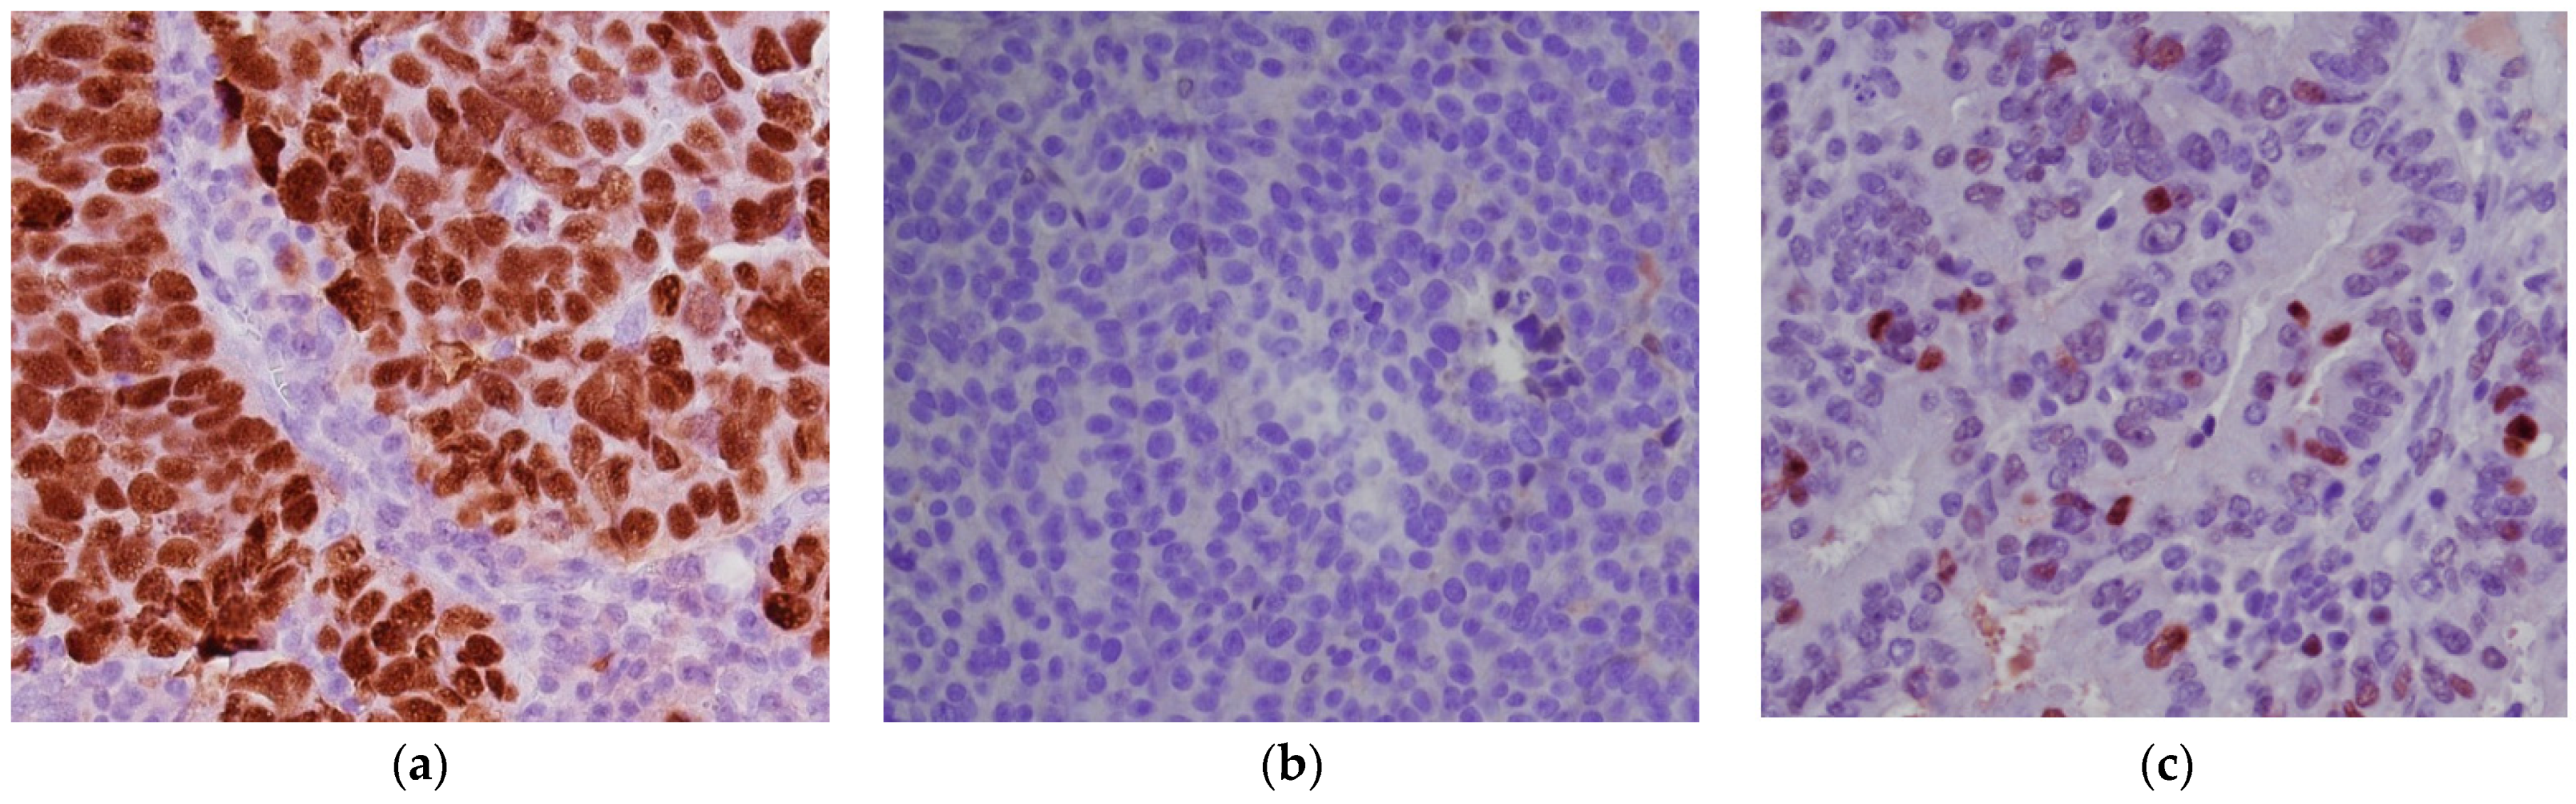

- p53 intense nuclear positivity in >80% tumor cells (overexpression pattern), complete absence of expression (null pattern) or cytoplasmic expression without nuclear staining were scored as p53 “abnormal” (p53abn) and correlated with TP53 mutation (Figure 2a,b).

- heterogeneous p53 expression was scored as “wild-type” (p53wt) and correlated with a TP53-wildtype gene (Figure 2c).